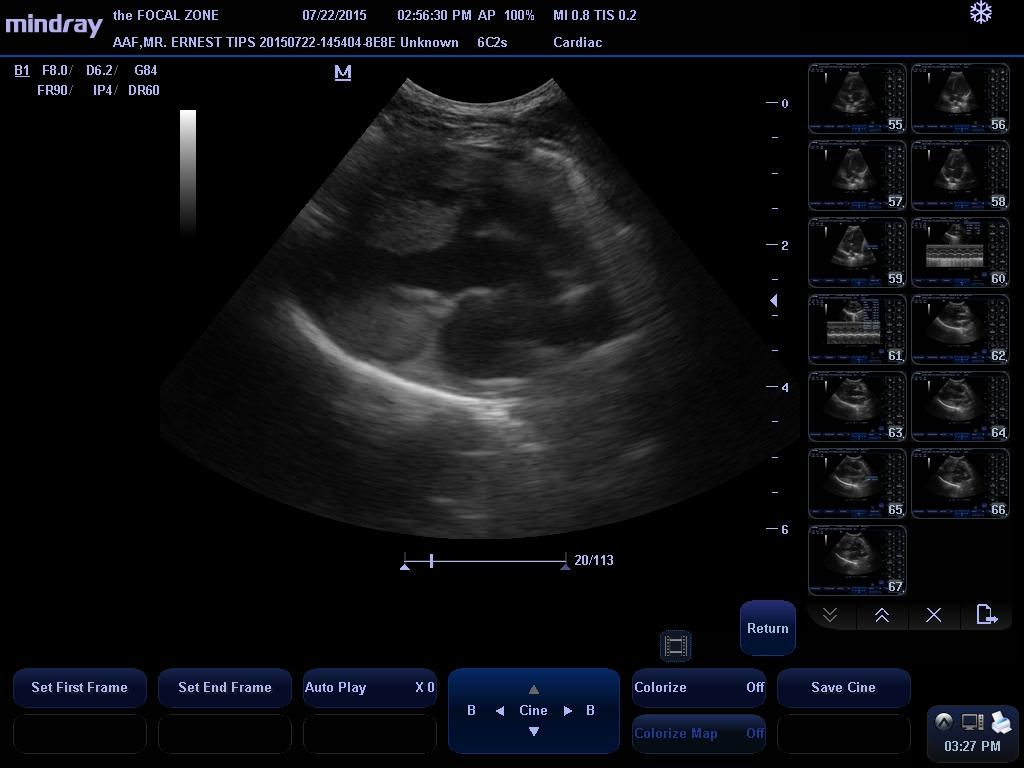

There is mild left atrial and left ventricular dilation. The mitral valve appears normal, though trace physiologic mitral regurgitation is present. Left ventricular wall thickness is normal. Left ventricular systolic function is normal. There is a small perimembranous ventricular septal defect present, with blood shunting from the left atrium into the right atrium. The velocity of shunt flow is consistent with the presence of a restrictive VSD. The aorta and aortic valve are normal. Right atrial and right ventricular dimensions are normal. The tricuspid valve subjectively looks normal, though mild tricuspid regurgitation is present. The pulmonary artery and pulmonic valve are normal. No pericardial effusion or cardiac masses are seen.

This examination demonstrates a small left to right shunting perimembranous ventricular septal defect with very mild left heart volume overload. The clinical significance of VSDs are dependent on the size of the defect and resistance to flow, which is related to the left and right ventricular systolic pressures. With small defects, there is a high resistance to systolic flow, and thus, there is only a small amount of blood that shunts through the defect, whereas with larger defects, there is a significant amount of shunting that can eventually lead to left-sided congestive heart failure and even shunt reversal if secondary pulmonary hypertension develops. This patient’s VSD appears to be small, and more importantly, his shunt velocity is consistent with a restrictive defect, indicating that the small size of the detect provides high resistance to flow, so that while his murmur is very loud, there is actually only a small volume of blood shunting from the left ventricle to the right ventricle (the loud murmur is caused by the blood squeezing through a small opening). Given the presence of a restrictive defect, it is possible that the VSD may never become clinically relevant, though the presence of mild left heart dilation suggests that his disease must be monitored carefully over time.